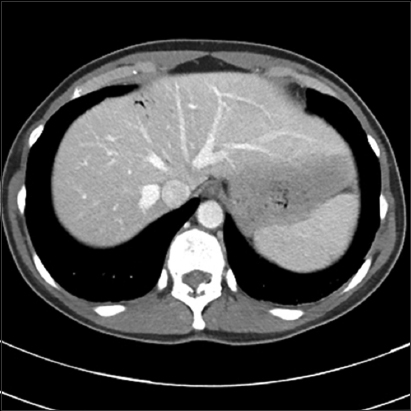

Chest x-ray findings include air in pulmonary artery, characteristic of pulmonary venous air embolism, pulmonary edema, adult respiratory distress syndrome, diminished vascularity in the upper lobes (air emboli common in upper lobes), intracardiac air, and atelectasis [47,48]. Computed tomography (CT) of the chest shows air in the pulmonary artery, heart and right ventricle [31,49,50]. CT of the abdomen can show air in the portal vein if the portal vein is cannulated (Fig. 3) [51]. CT of the brain shows intraparenchymal gas, midline shift, cerebral edema, and uncal herniation (Fig. 4) [52]. Magnetic resonance imaging (MRI) of the brain shows acute infarcts in the areas affected by air embolism [37]. Echocardiogram can identify air in cardiac chambers, patent foramen ovale (PFO), atrial septal defect, right ventricular dilation, decreased systolic function and pulmonary artery hypertension [53]. Transesophageal echocardiography (TEE) is more sensitive than transthoracic echocardiography in identifying PFO [54]. TEE is invasive, expensive and needs experienced personnel to do immediately [55]. Pulmonary embolism (PE) on TEE can be identified as global hypokinesis with mobile echogenic densities in the right atrium and right ventricle [40]. Precordial Doppler ultrasonography is sensitive in diagnosing air embolism and is noninvasive [56,57]. It is based on the principle that the Doppler ultrasonic signal from the transducer is reflected by moving red blood cells and cardiac structures, further electronically converted to an audible sound. The transducer is placed with a small amount of acoustic gel to the right side of the sternum between 3rd and 4th intercostal space, usually a few inches above the xiphoid process [58]. This position closely correlates with the placement of the transducer over the right atrium or right ventricle. Once the position of the transducer is confirmed it is secured with a circumferential rubber strap to avoid changes in Doppler signal with respiratory movements. A high pitched, “chirping”, “scratchy”, “roaring” sound is characteristic of air embolus [57]. A transient chirp is produced by small air embolus but raucous ‘static’ is usually produced by large air embolus. The disadvantage of precordial ultrasound Doppler is that it may be difficult to use in prone or lateral position [55]. Failure of Doppler signal can be due to slippage of the transducer especially in lengthy procedures or entrainment of air bubbles leading to decreased audible signal from the ultrasound [59]. Pulmonary artery catheter (PAC) can be used to detect air embolism. It is slightly more sensitive than etCO2, but it is invasive [59]. The increase in pulmonary artery pressure correlates with the amount and rate of air entrapment [55]. However, insertion of PAC is not practical in all cases as it needs more time and trained personnel and it is not well suited for aspiration of air from right atrium because of small atrial lumen [60,61].

thumblarge

Figure 3 Computed tomography scan showing portal venous air embolism (Image courtesy Akram Shabaan, MD)